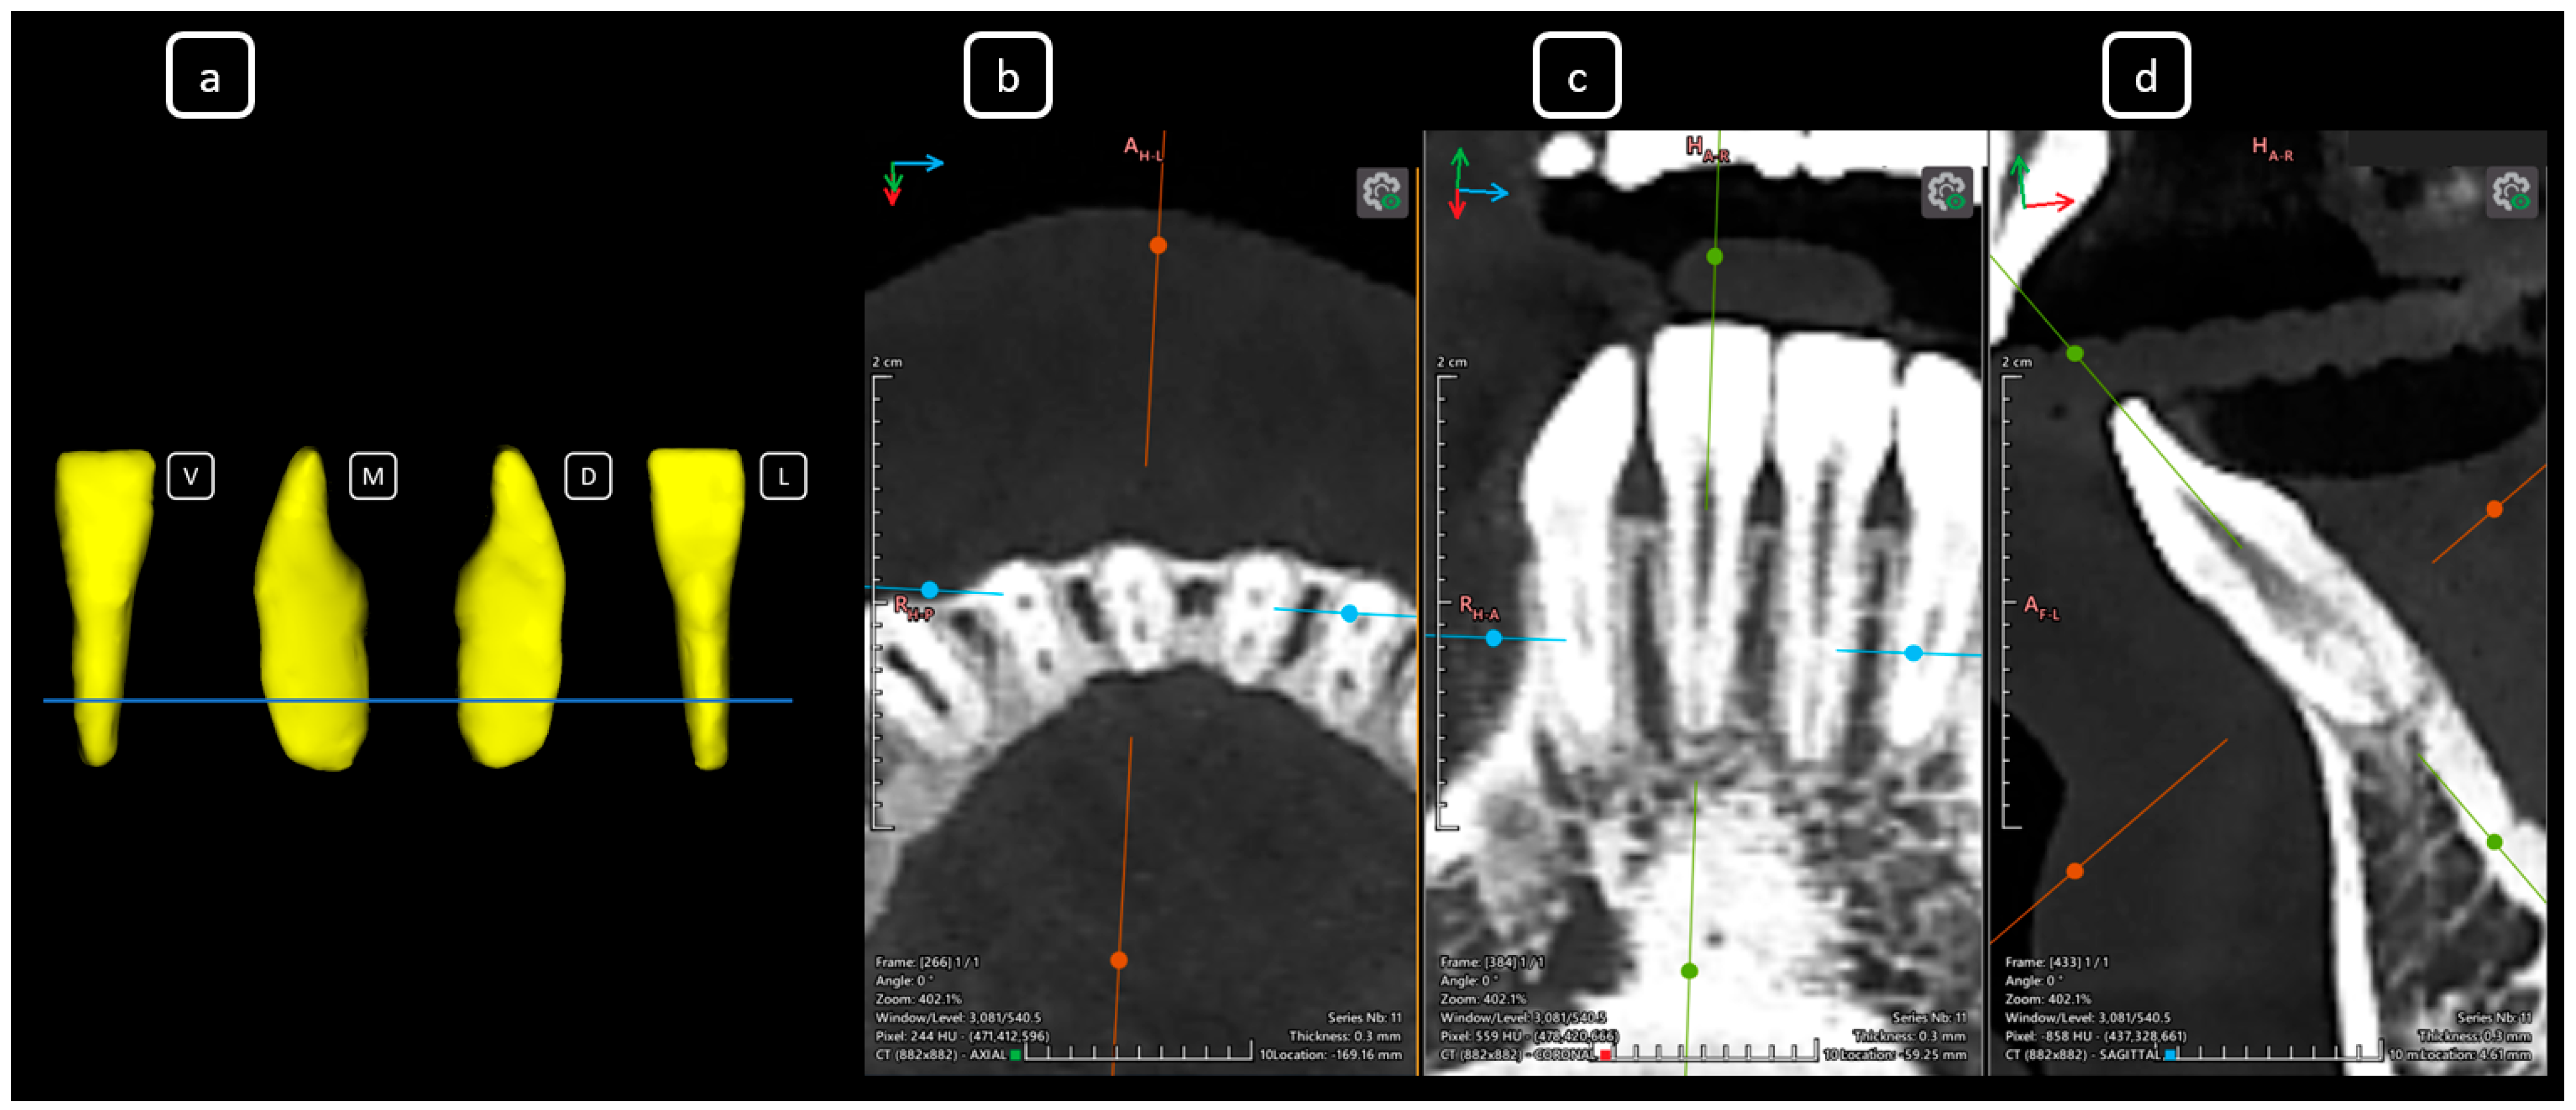

Imaging Findings of Clinical Significance in Endodontics During Cone Beam Computed Tomography Scanning of the Upper Airway—The Anterior, Bilateral, C-Shaped, Dual of Mandibular Root Canals: A Brief Case Report

García-Torres, E.; Guerrero-Falcón, D.L.G.; Bojórquez-Armenta, H.A.; Almeda-Ojeda, O.E.; Barajas-Pérez, V.H.; Solís-Martínez, L.J. Imaging Findings of Clinical Significance in Endodontics During Cone Beam Computed Tomography Scanning of the Upper Airway—The Anterior, Bilateral, C-Shaped, Dual of Mandibular Root Canals: A Brief Case Report. Diagnostics 2025, 15, 3157. https://doi.org/10.3390/diagnostics15243157